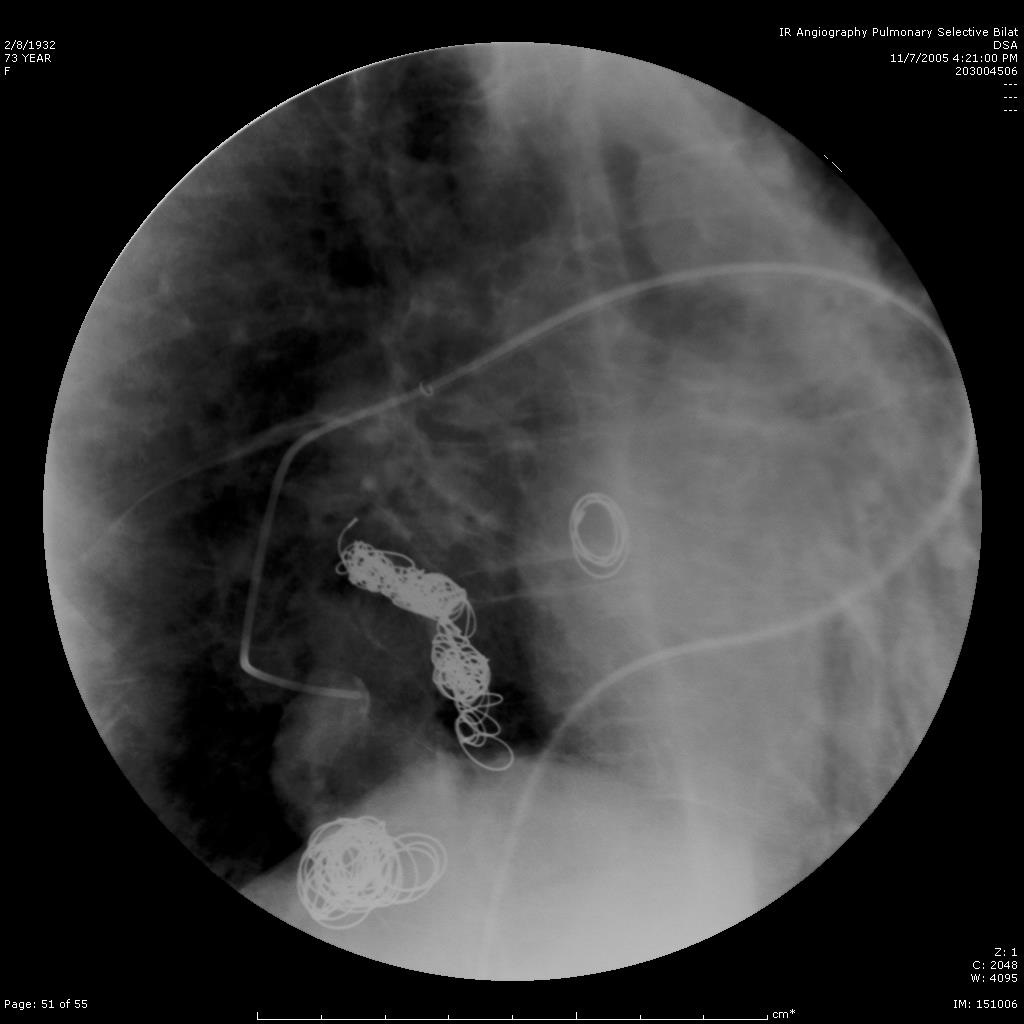

肺动静脉畸形

肺动静脉畸形分为单发、多发和弥漫性 |

这一例为多发性肺动静脉畸形 |

显示巨大静脉池显影 |

回流至肺静脉 |

选择其中一支畸形的滋养动脉 |

造影剂经静脉池回流至肺静脉 |

栓塞开始:先致密填塞静脉池,再致密栓塞滋养动脉 |

造影显示部分静脉池不显影,滋养动脉闭塞 |

选择性肺动脉造影显示另一支滋养动脉和静脉池。 |